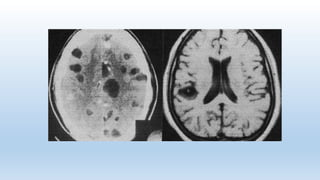

En general, la NCC se presenta como formas intraparenquimatosas,

asociadas con cuadros convulsivos, o formas extraparenquimatosas, estando

estas últimas asociadas con hipertensión endocraneana. Los quistes

intraparenquimatosos pasan por las siguientes fases:

fase vesicular: quistes viables, provocan una respuesta inflamatoria mínima.

fase coloidal: presencia de inflamación provocada por la respuesta

inflamatoria celular alrededor del quiste.

fase nódulo granular: sustitución gradual por tejido fibrótico y colapso

progresivo de la pared del quiste.

fase de calcificación: incorporación de calcio sobre el tejido fibrótico del

parásito

Fases del quiste. Engeneral, la NCC se presenta como formas intraparenquimatosas, asociadas con cuadros convulsivos, o formas extraparenquimatosas, estando estas últimas asociadas con hipertensión endocraneana. Los quistes intraparenquimatosos pasan por las siguientes fases: fase vesicular: quistes viables, provocan una respuesta inflamatoria mínima. fase coloidal: presencia de inflamación provocada por la respuesta inflamatoria celular alrededor del quiste. fase nódulo granular: sustitución gradual por tejido fibrótico y colapso progresivo de la pared del quiste. fase de calcificación: incorporación de calcio sobre el tejido fibrótico del parásito